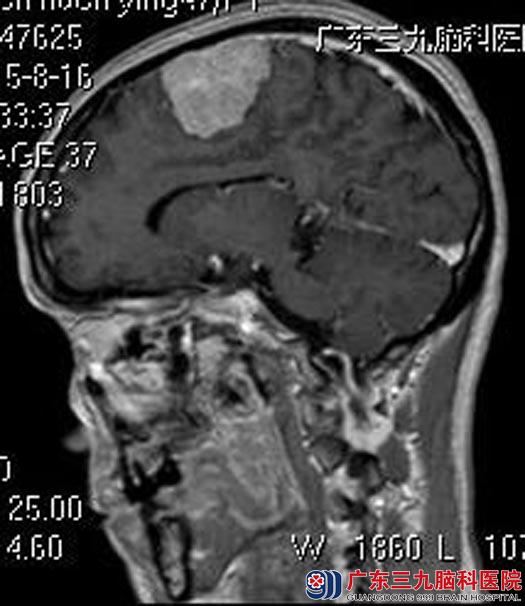

获知病情后,他直奔广东三九脑科医院。进一步头颅MR检查结果:左侧额顶部大脑凸面镰旁占位,大小约为4.7cm×4.0cm×3.0cm,考虑脑膜瘤。

完善相关检查后,由综合神经外科鲁明主任主刀,在全麻下行左额镰窦旁脑膜瘤切除术,显微镜下见肿瘤部分呈灰白色胶状,部分质地中,血运一般,与脑组织边界较清,予以全切,肿瘤下极粗静脉完整保留,手术顺利。术后王医生无明显的功能障碍,康复出院。术后病理结果:脑膜皮细胞型脑膜瘤(WHO I级)。

▲手术前